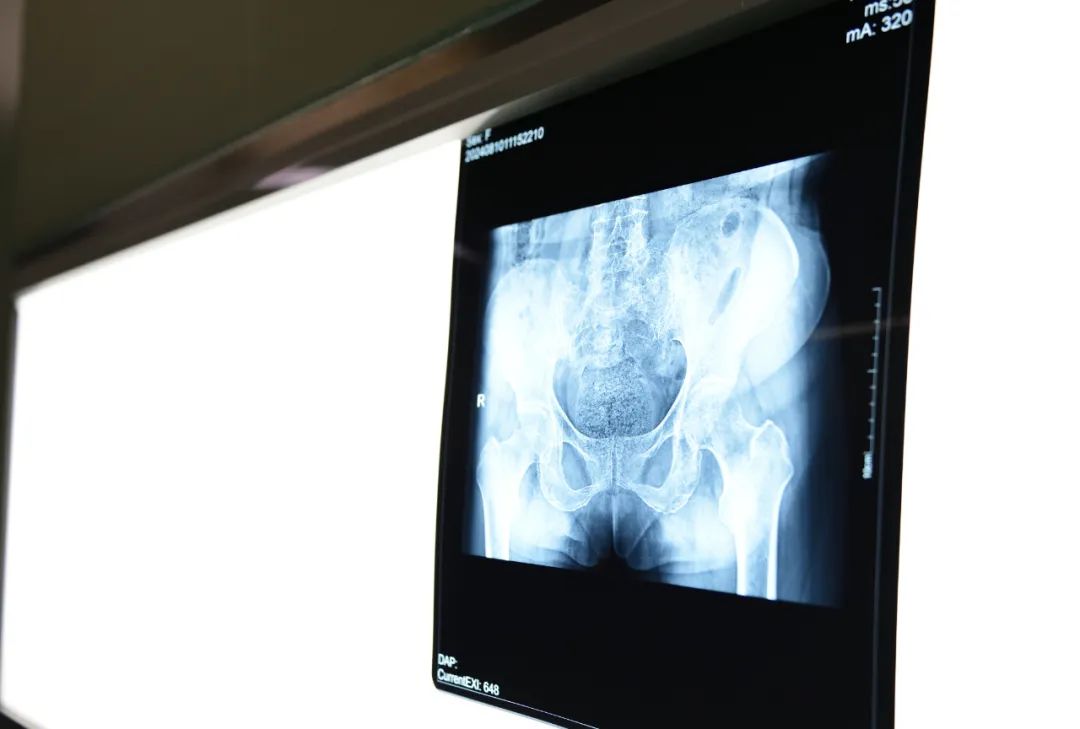

7月12日,70岁高龄患者鞠婆婆找到骨一科主任费熹,拉住费主任的手,泪眼婆娑地说道,"费主任,你可得帮帮我啊......痛,钻心的痛,完全下不了地,我有时躺在床上一点都不敢动"。原来,鞠婆婆有糖尿病的既往病史,曾经做过髋关节置换手术,综合年龄、基础疾病等原因曾被多家医疗机构建议保守治疗,在成都就医过程中,因无法承担巨额医疗费用而选择回什就医。

看着鞠婆婆痛苦的样子,费主任一边安慰着鞠婆婆,一边着手准备手术事宜。为确保手术的安全精准实施,骨一科联合重症医学科、麻醉科等科室开展MDT多学科会诊,针对鞠婆婆的病情设计出严谨的手术方案。 7月15日,在骨一科主任费熹带领下,骨科医疗团队为鞠婆婆实施了右髋关节假体翻修术。“虽然知道手术难度会很大,但是手术中的情况比我们想象中更难,”所有参与手术的医生感慨地说道。

01髋臼和转子间有着大量的骨溶解,需要重新进行植骨处理,同时免造成骨折。

03髋臼外杯已经穿透进入盆腔中,在处理过程中稍有不慎便会导致肠道等脏器以及血管的损害